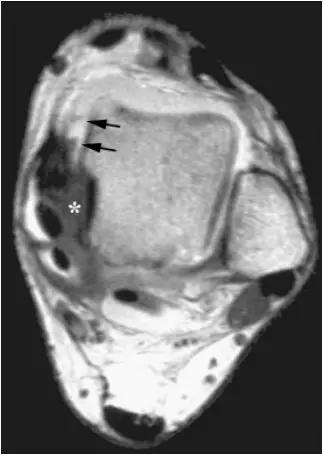

轴位示意图示后内侧撞击综合征:M:内踝;L:外踝;TP:胫后肌腱;FDL:趾长屈肌腱;Talus:距骨。短箭:距骨胫骨间肌腱深层纤维;箭头:距骨胫骨间肌腱后部纤维。

X线平片示胫骨后部骨赘形成,MR质子像黑箭示胫骨内后侧骨赘形成,白箭示内后侧软组织增厚, 白箭头:胫后肌腱;黑箭头:趾长屈肌腱